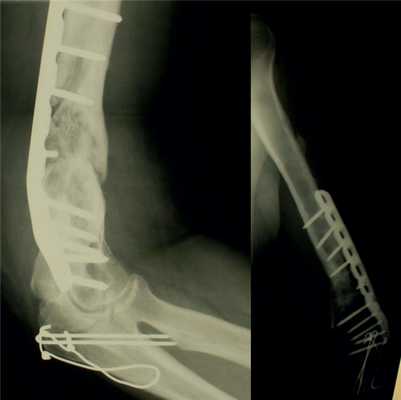

У остальных пациентов 1-й группы внутренние фиксаторы и фиброзные ткани между фрагментами удаляли во время операции, производили адаптацию костных фрагментов с восстановлением оси сегмента и выполняли накостный остеосинтез (или реостеосинтез).

Основная концепция реконструктивной операции - хорошая биологическая совместимость имплантата и хирургическая техника, обеспечивающая бережное отношение к мягким тканям и костным фрагментам. Для остеосинтеза (или реостеосинтеза) использовали оригинальные накостные пластины: динамические компрессирующие (DCP), динамические компрессирующие ограниченного контакта (LC-DCP) и пластины с угловой стабильностью (LCP).

В одном наблюдении произошел перелом фиксатора с формированием ложного сустава. У всех остальных пациентов достигнута полная консолидация перелома с хорошим функциональным результатом.